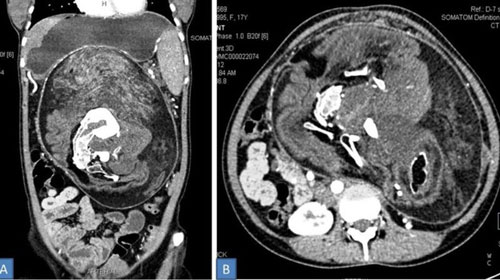

Thấy bụng cậu con trai mới chào đời được 4 tháng ngày càng phát triển lớn, phụ huynh đưa tới bệnh viện thăm khám. Kiểm tra hình ảnh, các bác sĩ phát hiện một khối thai chiếm hết nửa bụng bên phải của bệnh nhi.

Các bác sĩ đã lấy ra một bào thai không còn khả năng sống sót ra khỏi cơ thể của một cậu bé mới 15 tuổi.

(DNVN) - Các bác sĩ của bệnh viện huyện Midnapore, bang Tây Bengal, Ấn Độ đã bị sốc khi phát hiện bào thai chết lưu trong bụng một cậu bé 4 tuổi nhập viện vì đau bụng.

(DNVN) - Mới đây, một cậu bé 4 tuổi ở Ấn Độ được phát hiện là đang mang thai và bào thai đã phát triển được một phần.

(DNVN) - Tờ chinadaily (Trung Quốc) đưa tin, các bác sĩ đã phát hiện một song thai đang ký sinh trong bụng em bé 8 ngày tuổi.